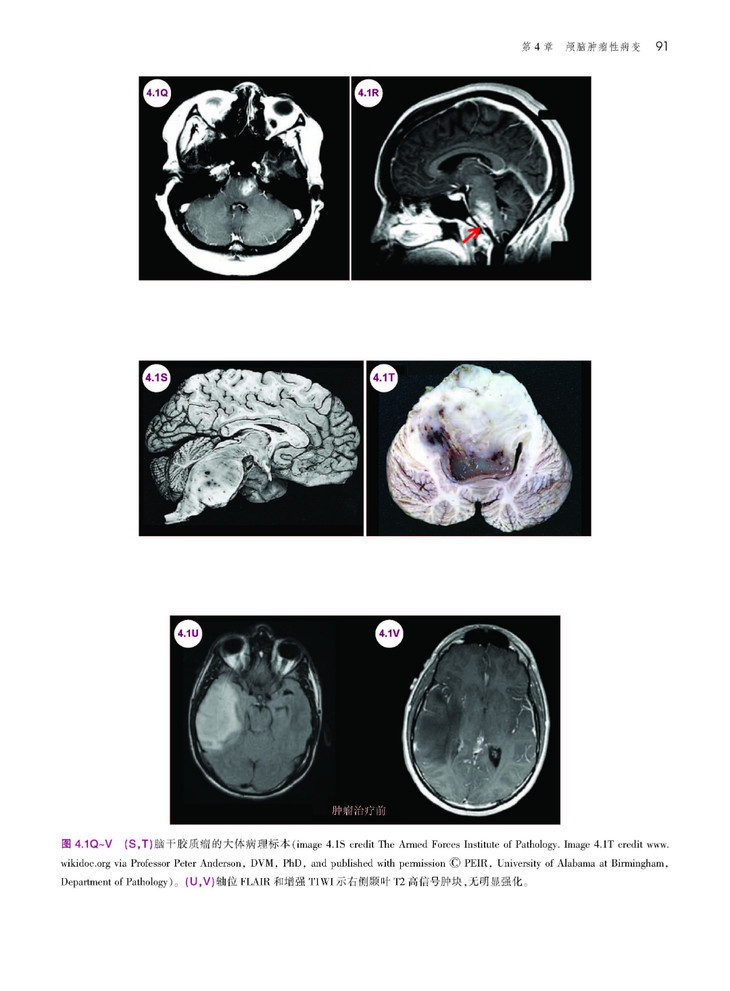

本书是一部极具实用价值的神经系统疾病影像学著作。作者以典型临床病例入手,对疾病发生、影像学和诊治经过进行阐述,并对影像学表现及临床病理机制进行了较为详细的解析,举一反三,扩展并深化了对每一类神经科疾病的认识和理解。本书共列举了超过170个临床病例,涵盖了癫痫、脑血管病、感染、自身免疫疾病、脱髓鞘性疾病、创伤性脑病、神经系统变性疾病和神经系统肿瘤等疾病,内容丰富而全面,且每个病例均资料翔实,条理清楚,行文流畅,图片精美,是神经病学领域难得的一本好书,也是神经科和影像科医师进步与提高不可或缺的专业著作。

本书可以说是一本一体化指南,为神经科医师提供了临床背景下的详细、典型神经影像学病例。作者合理编排本书,通过超过170个病例、1500余幅图像,以影像学表现作为讨论病理生理学、临床表现和疾病诊疗的平台。本书以神经学从业者或学生的角度编写,用易于阅读的形式概述了每种疾病,并配有丰富的图像,从而帮助准确识别和治疗常见、罕见神经疾病。本书共分为15章,涵盖神经病学的主要领域,包括卒中、出血、肿瘤、癫痫、创伤、神经退行性疾病、感染性疾病和儿科病症等。每种疾病均以简要病例和影像学诊断开始,然后是疾病概述、临床表现、影像学表现和诊断、鉴别诊断和治疗。本书通过大量有相似影像表现的病例,以增强神经科医师解读MRI、CT、MRA、血管造影、脑电图、大体和显微神经病理学图像的信心。